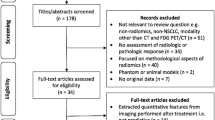

Overall, 14 patients were recruited (mean age, 67 years +/− 12, 8 men). They had 22 tumours between them, comprising 12 primary lung cancers, 8 metastatic lymph nodes in the thorax and 2 distant metastases within the field of view. Details of the patients, their demographics and their lesions are presented in Table 1. All patients had either completed induction chemotherapy or were not eligible for chemotherapy, except for patient 4 who underwent concurrent chemoradiotherapy. Therefore, changes in MRI biomarkers were considered largely due to radiation. Sample images are shown in Fig. 1.

Histograms revealed skewed, distributions of all MRI biomarker parameters that deviated from normality except for pre-treatment median IAUC60 and pre-treatment median ve (Fig. 2A, B and Supplementary Table S1). Bland-Altman plots in test-retest baseline MRI biomarker data (Fig. 2C) showed that measurement error was only constant over the range of biomarker values for median IAUC60. Consequently, all biomarkers underwent a logarithmic transformation.

Histogram distributions of the cohort parameter values for each of the six MRI biomarkers at (A) pre-treatment baseline and (B) week 2 of treatment. Measurement error of the test-retest replicates pre-treatment is shown in C with Bland-Altman plots, where the top and bottom dotted lines indicate LOA